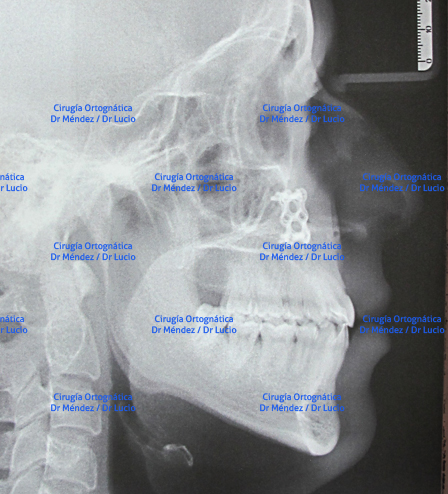

RETROGNASIA E HIPOPLASIA DEL MENTÓN Paciente operado de avance de mandíbula y mentoplastia de avance |

||

![]() |

|